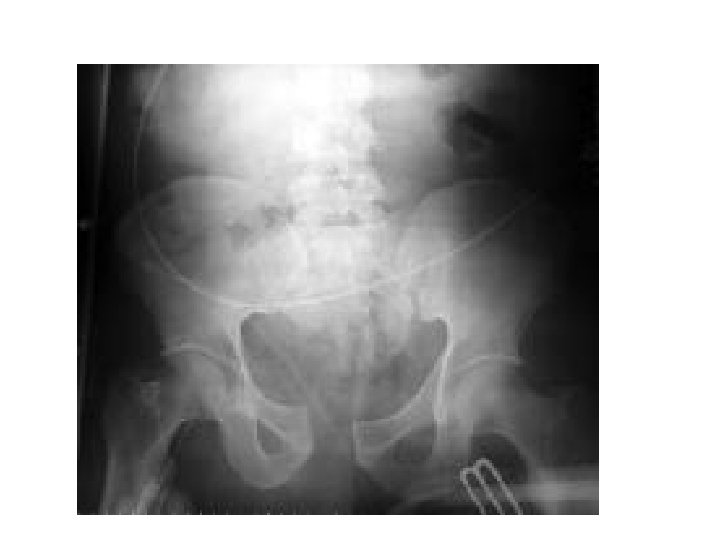

Pelvis-Vertebra • Pelviste kırık, kanamayı değerlendir • KÜTÜK ÇEVİRME (3 -4 kişi ile) • Tüm spinöz proseslere dokun Vertebra grafileri Pelvis grafisi

Travmada Acil Radyoloji • Lateral servikal (C 1 -7, T 1) • AP akciğer • AP pelvis * Servikal AP ve odontoid * Yatak başı USG * BBT